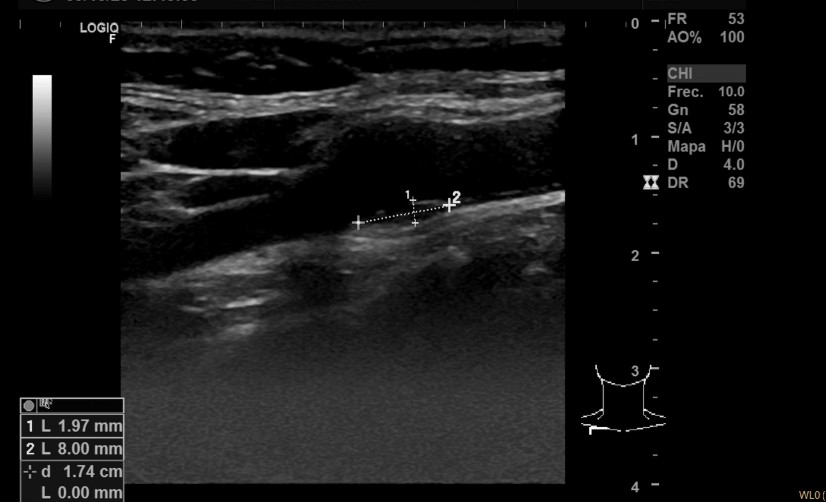

Descripción de los hallazgos ecográficos y las imágenes más relevantes para la resolución del caso: Ecografía multivaso: Placa translúcida de 1,97 x 8 mm en bulbo de carótida derecha, placa translúcida de 6,56 x 2,11 mm en carótida izquierda, placa hiperecogénica de 7,7 x 3,12 mm en femoral derecha. Aorta normal.